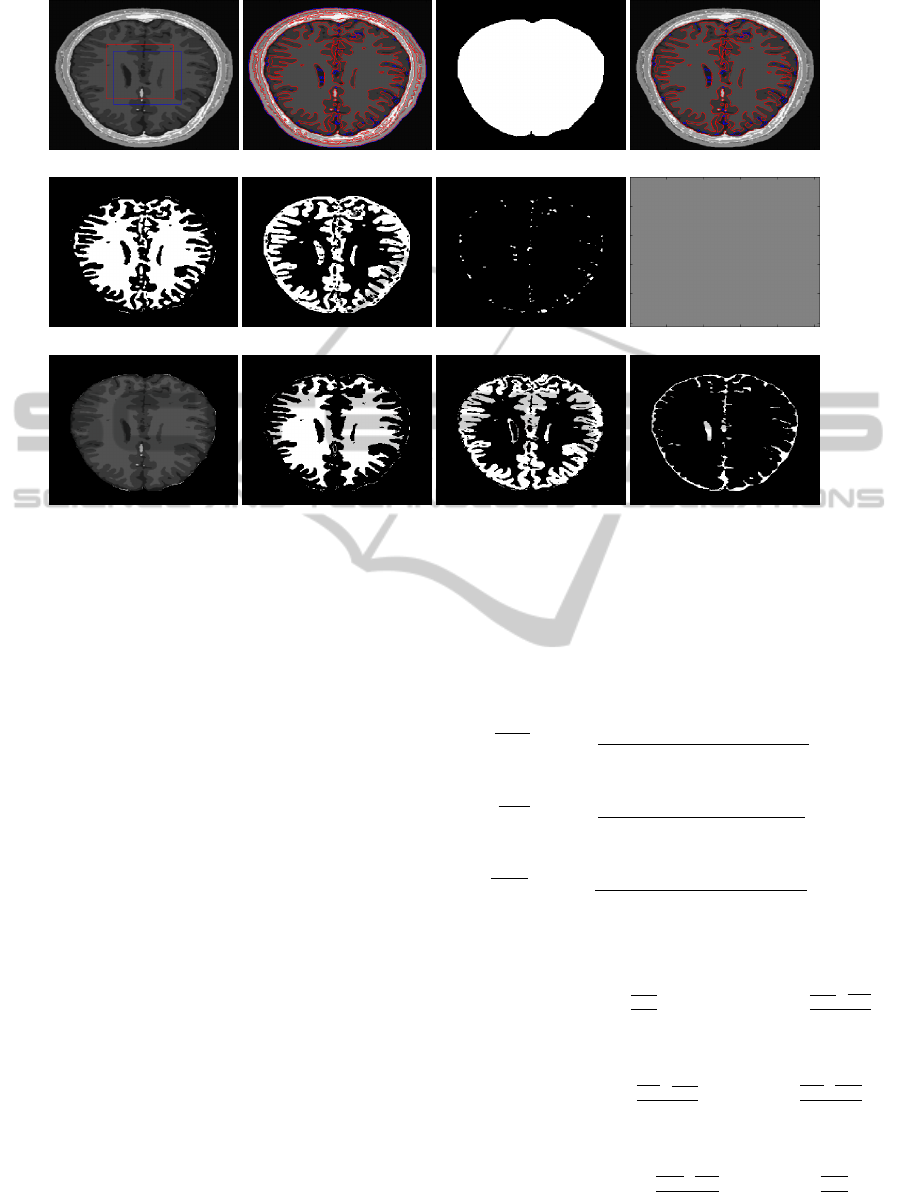

Segmentation of brain MRI images into distinct and

non-overlapping regions, such as WM, GM and CSF,

is a challenging problem due to the geometric com-

plexity of the regions to be segmented. The pres-

ence of noise and intensity inhomogeneity in the im-

age significantly increases the complexity of the prob-

lem. Since, there are three important regions (WM,

GM and CSF) in the brain area, a four-phase level

set method is necessary for segmenting the image into

three or four regions. This paper presents a four-phase

region based active contour method that segments an

MRI brain image into WM, GM and CSF regions with

a good accuracy. It uses both local and global inten-

sity averages in the definition of an energy functional,

such that local intensity mean values help the pro-

posed model to segment regions with intensity inho-

mogeneity, whereas global intensity mean values are

responsible for segmenting the homogeneous areas in

the image. In addition, a pixel correction method

based on simple thresholding is applied in order to

correct wrong pixels.

Another research goal is the development of an auto-

matic technique to extract the brain area necessary for

intersecting the obtained level sets, thus avoiding the

hand-drawn binary mask utilized in the second stage

of the proposed technique.